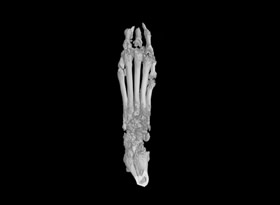

用于骨質(zhì)疏松和關(guān)節(jié)炎動物模型潛伏期的骨結(jié)構(gòu)和密度改變的研究。MicroCT是目前研究骨立體結(jié)構(gòu)、容量和微結(jié)構(gòu)細微改變較好方法。

1.掃描重構(gòu):常規(guī)樣本,一個視野可以掃的樣本,按以上報價。對于一些特殊樣本或較大樣本,可能需要多個視野掃,費用按相應(yīng)的視野數(shù)計算,比如大鼠爪子至少需要3個視野。